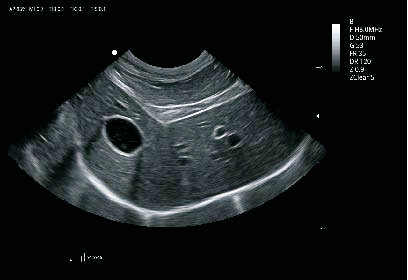

卓越的图像质量